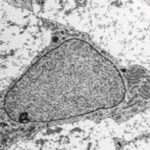

¿Qué es la osificación?

La osificación es un proceso complejo que involucra la transformación de tejido conectivo diferenciado en tejido óseo. Este proceso se lleva a cabo a través de una serie de fenómenos…